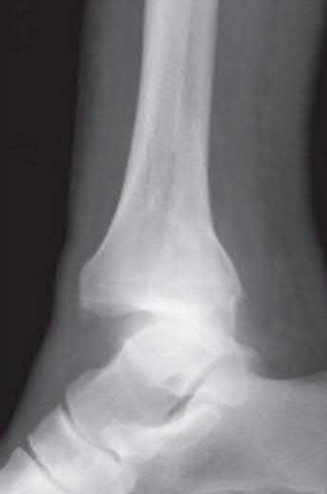

A 34-year-old male sustains the closed injury seen in Figure A as a result of a high-speed motor vehicle collision. What is the most appropriate next step in treatment?

The radiograph shows a comminuted pilon fracture, which is associated with high-energy trauma and significant soft tissue injury. The tested concept here is the importance of avoiding definitive reduction and fixation of this high-energy injury, which has been shown to be associated with an increased risk of wound complications and deep infections (as compared to staged treatment with usage of a spanning external fixator).

Patterson et al. reviewed 23 consecutive patients with comminuted distal tibia fractures. They showed 0% infections or wound-healing problems in their patient population treated with a two-staged protocol. Their protocol involved fibula fixation with an intramedullary implant and application of a medial external fixator to to regain length and restore anatomic alignment. Reevaluation of the limb occurred ten to fourteen days later for definitive fixation.

Sirkin et al. retrospectively reviewed 40 closed and 17 open pilon fractures (AO types 43A-C) that were treated with staged surgical management (avg. time from ext. fix. to formal reconstruction was 14 days (range 4 to 31) They reported 17% post-operative wound complication in the closed group and 11% post-operative wound complication in the open group (Gustilo Type I-III). They suggest the technique was successful in both closed and open pilon fractures.